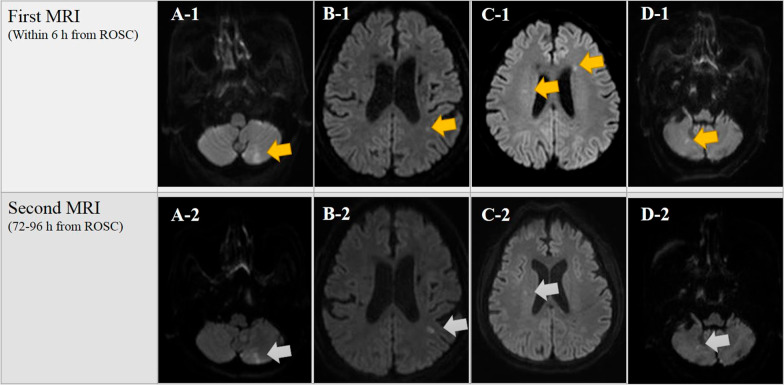

Fig. 2.

Patients excluded from this study despite DW-MRI showing the presence of HSI. Our institution's targeted temperature management protocol recommends but does not require obtaining two brain MRI scans within 6 h (first MRI) and between 72 and 96 h (second MRI) after ROSC. In this study, 4 patients showed only 1 or 2 focal HSI (orange arrow) on the ultra-early DW-MRI, and all of them did not exhibit an expanded HSI (gray arrow) area in the DW-MRI 3–4 days after ROSC. They all showed good neurological outcome, and among them, cases A, B, and D showed higher CPC scores (CPC 1) compare with case C (CPC 2). Abbreviations: CPC, cerebral performance category; DW-MRI, diffusion-weighted magnetic resonance imaging; HSI, high-signal intensity; MRI, magnetic resonance imaging; ROSC, return of spontaneous circulation

Cytotoxic edema due to brain injury after acute CA shows HSI in DW-MRI with corresponding low ADC from a very early time [32, 33, 38, 39]. On the other hand, it is a potentially valuable predictor of good neurological outcome if AHSI is observed on DW-MRI. However, compared to other studies, only our previous and this study have shown 100% specificity when predicting poor neurological outcomes using the presence or absence of HSI in DW-MRI [17, 18]. We speculated different results based on determining the single or multi-focal HSI results in DW-MRI as positive/negative. The reason we excluded these findings from this study can be explained as follows. First, Oh et al. have reported that single focal HSI or absence of HSI in DW-MRI performed immediately after the rewarming phase of TTM showed a good neurological outcome [23]. Second, our previous studies showed that, if HSI was present in ultra-early DW-MRI, the HSI area appeared to expand in DW-MRI after 72 h of ROSC, which was because the occurrence of brain edema post-CA brain injury was time-dependent [9, 18]. That is, there is a difference between single lesion or multiple HSI which corresponds to specific vascular territories as opposed to a diffuse spread throughout the cerebral cortex or deep gray matter that can be viewed as post-CA brain injury. In the present study, four patients with 1–2 focal HSI observed in ultra-early DW-MRI were excluded as undetermined. All of them showed good neurological outcomes with 1–2 focal HSIs in which the HSI area had not expanded, on DW-MRI 3–4 days after ROSC. However, our conclusion that focal HSI shows good neurological outcomes cannot be generalized as our study involved only a small number of patients from a single center. Nevertheless, if neurological outcomes following DW-MRI are to be predicted according to the presence or absence of HSI, we consider it advisable to exclude focal HSIs as being undetermined until the results of a multicenter large-scale study are obtained and to use other predictive tools in the meantime.